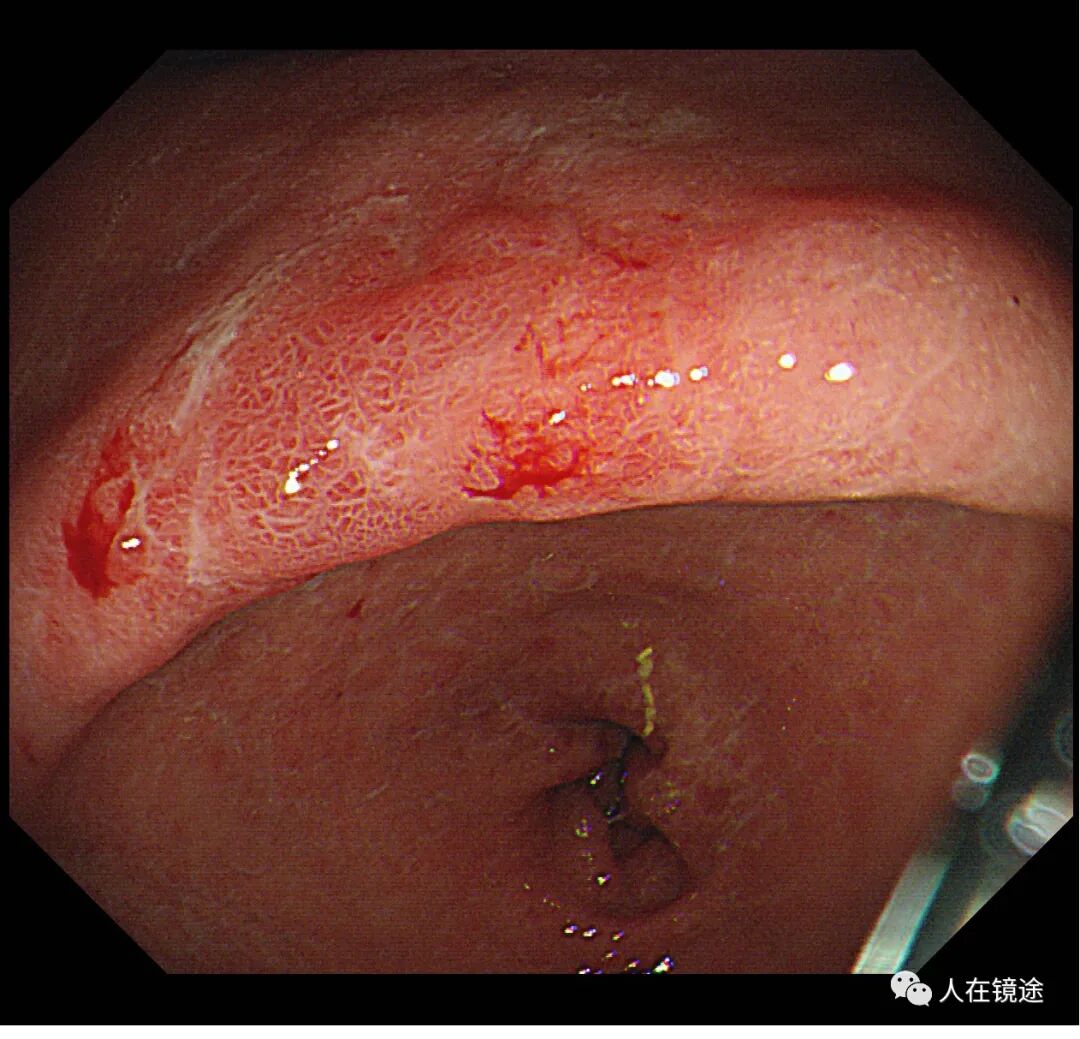

白光示胃窦小弯见一0.8*1.2cmIIa粘膜发红病变,表面粗糙

白光+近焦示:胃窦小弯见一0.8*1.2cmIIa粘膜发红病变,微结构稍紊乱,表面粘膜高低不平伴自发性出血。